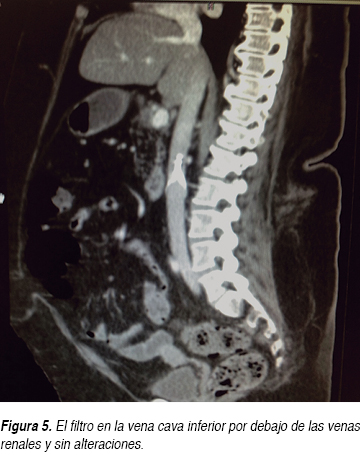

Durante su estancia hospitalaria la paciente presentó mejoría clínica, disminuyendo las cifras de presión arterial a valores normales tras ajustar el tratamiento antihipertensivo con losartán, nifedipino de liberación prolongada, nitratos orales, hipolipemiantes orales, sulfonilurea y metformina. Se incrementó la dosis de warfarina desde su ingreso a piso. Posteriormente, tras la desaparición del dolor subesternal y con la disminución de la disnea, se le pidió una ecografía de cuatro extremidades para ser realizada en un hospital de tercer nivel, sin embargo, sólo se reportó la ecografía Doppler color con enfoque en sistema venoso de miembros inferiores, sin documentarse anormalidades significativas que indicaran trombosis venosa profunda (TVP) en miembros inferiores; aunque cabe aclarar que clínicamente no presentaba dolor o datos sugestivos de tromboflebitis en extremidades superiores. Posteriormente se le solicitó a la paciente una angiotomografía de arteria pulmonar (Figuras 3 y 4), donde se demostró la presencia de un trombo (infarto pulmonar) en las ramas segmentarias de la arteria pulmonar superior derecha con datos de canalización parcial y sin imagen de semiluna, la cual orientó a pensar en un trombo crónico. No se reportaron anormalidades en el FVCI (Figura 5). La paciente fue egresada por mejoría clínica cinco días después de su hospitalización y la relación internacional normalizada (INR) a su egreso hospitalario se reportó en 3.5.